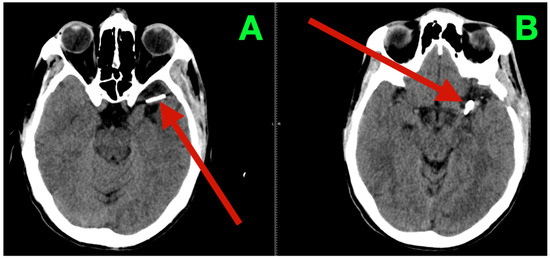

Immediate postoperative neuroimaging was not obtained, consistent with the institutional protocol in neurologically stable patients after uncomplicated microsurgical aneurysm clipping. Predefined triggers for urgent imaging—any new focal deficit, sustained escalation of headache, decline in level of consciousness, or refractory hypertension—did not occur during inpatient monitoring. The patient was discharged on postoperative day three with instructions regarding blood pressure control, wound care, graded activity progression, and scheduled outpatient visits at two weeks, six weeks, and three months. At interval clinic assessments, he reported complete resolution of the preoperative vascular-pattern headaches, absence of exertional provocation, and restored confidence in balance and sustained fine-motor endurance during overhead tasks. The neurological examination remained normal and unchanged from the inpatient baseline. At three months, non-contrast cranial CT (Figure 3) demonstrated the expected clip artifacts at the MCA bifurcation and proximal M1 with preserved parenchymal attenuation throughout the superior division territory and within the internal capsule and dorsal basal ganglia, without encephalomalacia, hydrocephalus, or extra-axial collection, radiologically corroborating durable exclusion of both aneurysms with intact branch and perforator perfusion. Functional outcomes were congruent with the radiology and clinical course: the patient met criteria for complete independence with a modified Rankin Scale score of 0 and National Institutes of Health Stroke Scale (NIHSS) of 0 at discharge and again at the three-month follow-up.

Figure 3.

Three-month postoperative non-contrast cranial CT. (A) Axial non-contrast CT at the level of the left MCA bifurcation/insular apex, showing the expected clip artifact centered on the bifurcation–proximal M1 complex, with preserved cortical ribbon along the opercular–insular corridor, normal attenuation of the internal capsule and dorsal basal ganglia, and no peri-clip hypodensity, hemorrhage, or mass effect. (B) Axial non-contrast CT at a slightly higher level through the superior division territory, demonstrating intact suprasylvian cortex and corona radiata without encephalomalacia or gliotic change. Ventricles and basal cisterns are normal in size and configuration, midline is preserved, and there is no extra-axial collection.

The durable resolution of preoperative micro-asymmetries, together with structurally preserved dominant-hemisphere parenchyma on the three-month CT, supports effective clip reconstruction with maintained superior-division branch flow and uncompromised lenticulostriate perfusion.